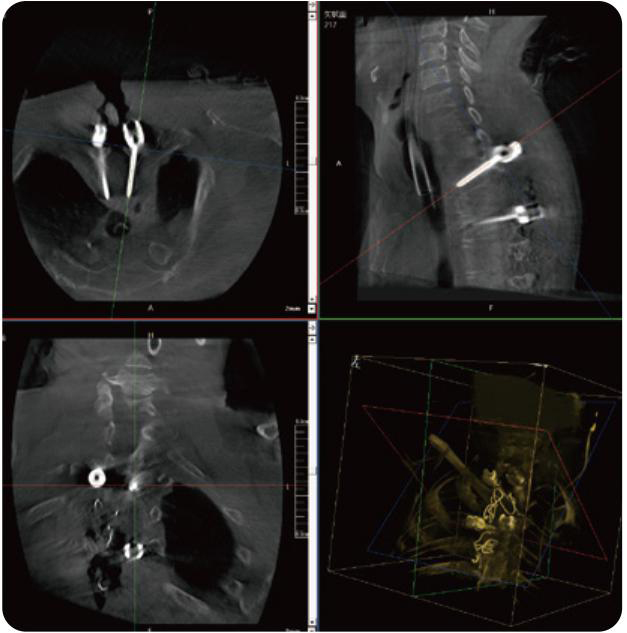

PL300B可應用于多節段脊柱外科手術,輔助醫生定位病灶部位,為脊柱外科手術(經皮椎體成形術、椎弓根螺釘內固定術等術式)提供術前手術流程規劃、入釘位置、角度可視化引導,模擬仿真入釘輔助。

PL300B搭配普愛醫療自主研發生產的平板3D C形臂,借助一體化自適應配準( 軌跡配準)技術,通過追蹤C形臂三維采集軌跡,自動完成圖像坐標建立和系統坐標配準。配準精度更高,操作步驟少,系統運作效率高。